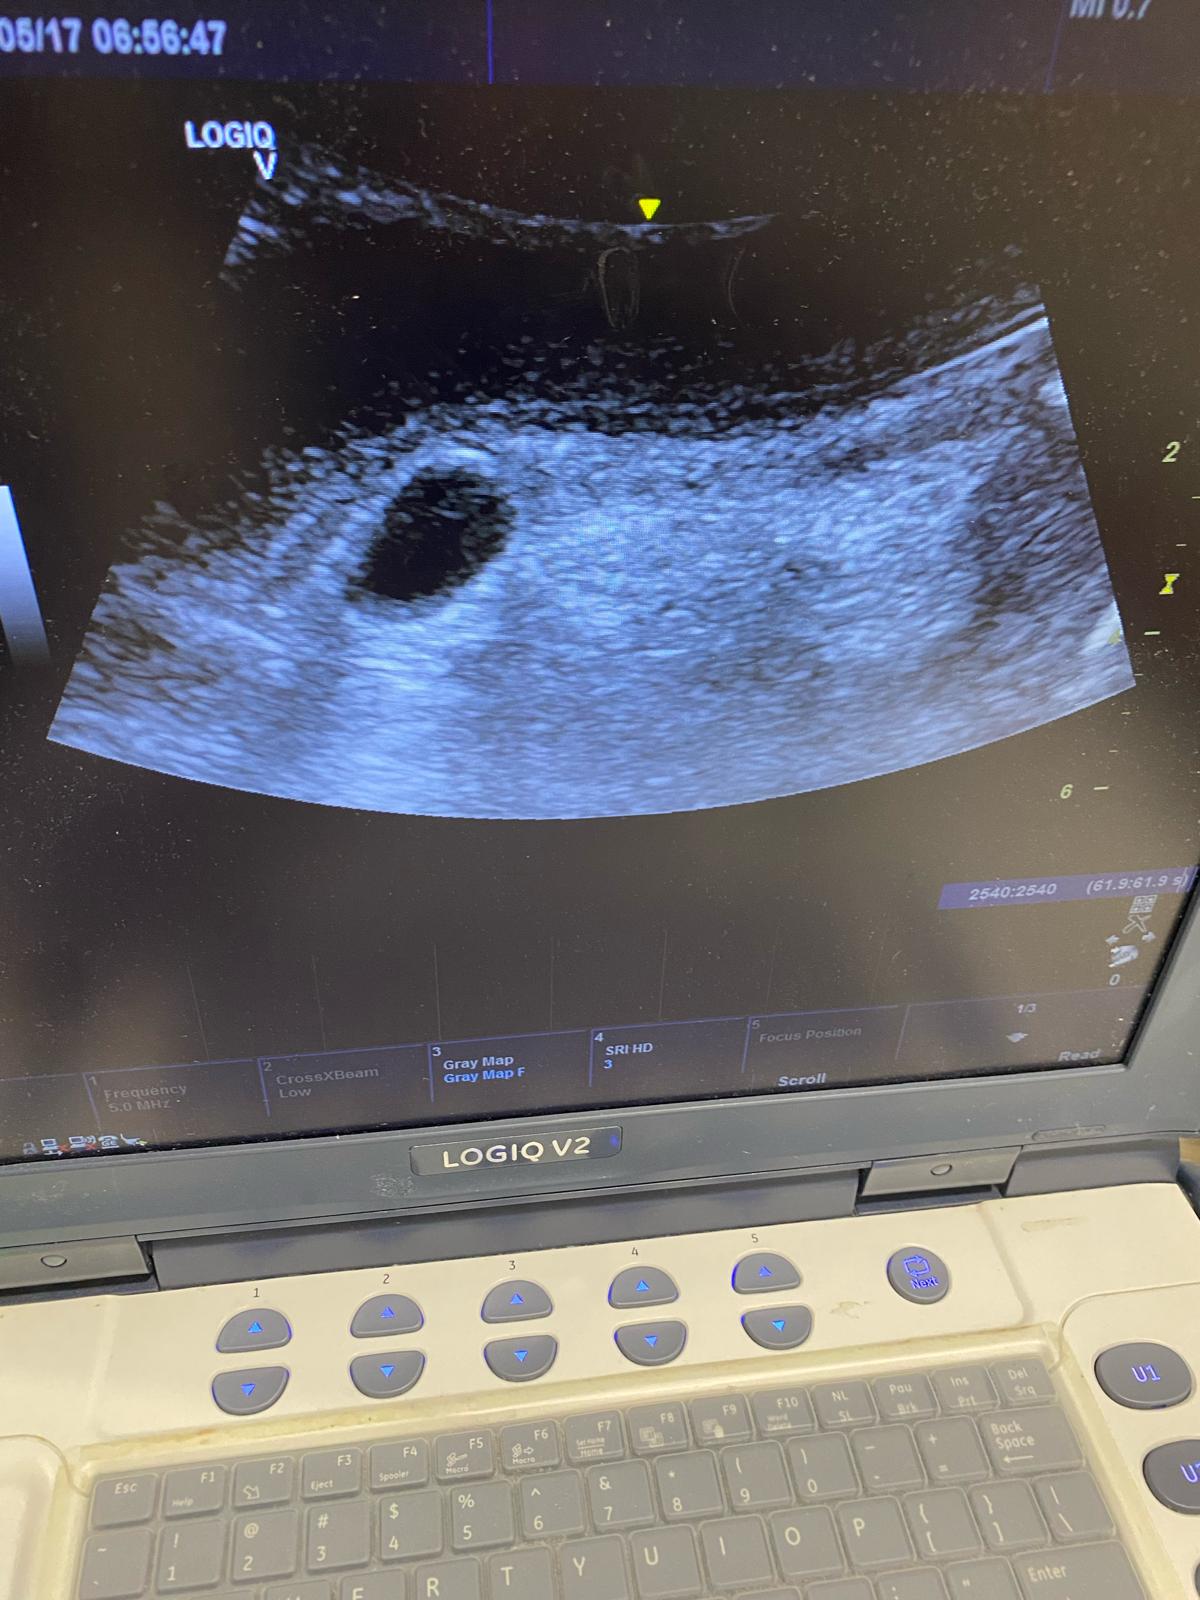

Vejiga distendida alcanzando mesogastrio, sin observar en su interior el balón de la sonda vesical. Al continuar la exploración, realizamos un corte longitudinal de la uretra peneana en el que podemos observar el balón de la sonda vesical en la parte proximal de la uretra.

Se concluyó anuria de causa obstructiva a nivel de uretra peneana por balón vesical mal posicionado.

Se desinfló el balón y se avanzó la sonda, bajo control ecográfico, hasta vejiga, recuperando una buena diuresis.